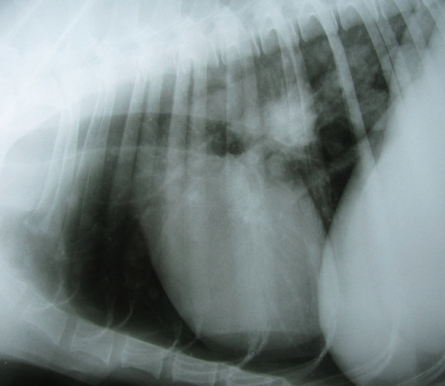

A usted le llega un paciente canino Ovejero Alemán de 8 años de edad “Laica” con los signos que observa en la fotografía. Al examen neurológico se observa hipermetría, ataxia y tendencia a la rigidez en la marcha. Además el paciente demuestra disnea mixta, con 2 semanas de evolución. Se decide realizar una tomografía cerebral y Rx. de tórax (ver imágenes).

Marque la alternativa correcta respecto a las imágenes.

a) El paciente padece probablemente de tumor cortical y metástasis pulmonar

b) El paciente posee probablemente de metástasis cerebelar y pulmonar

c) El paciente padece de granulomas encefálicos y micosis pulmonar.

d) El paciente presenta un síndrome vestibular y neoplasia pulmonar

e) El paciente padece solamente de neoplasia pulmonar perihiliar